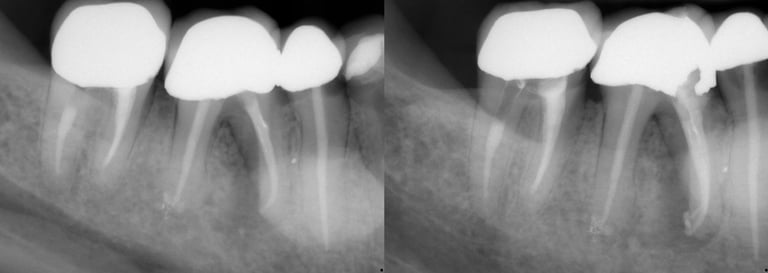

Gallery 1: Initial Cases

Initial Root Canal Cases with preoperative and postoperative radiographs.

#31 RCT

#5 RCT with 3 canals